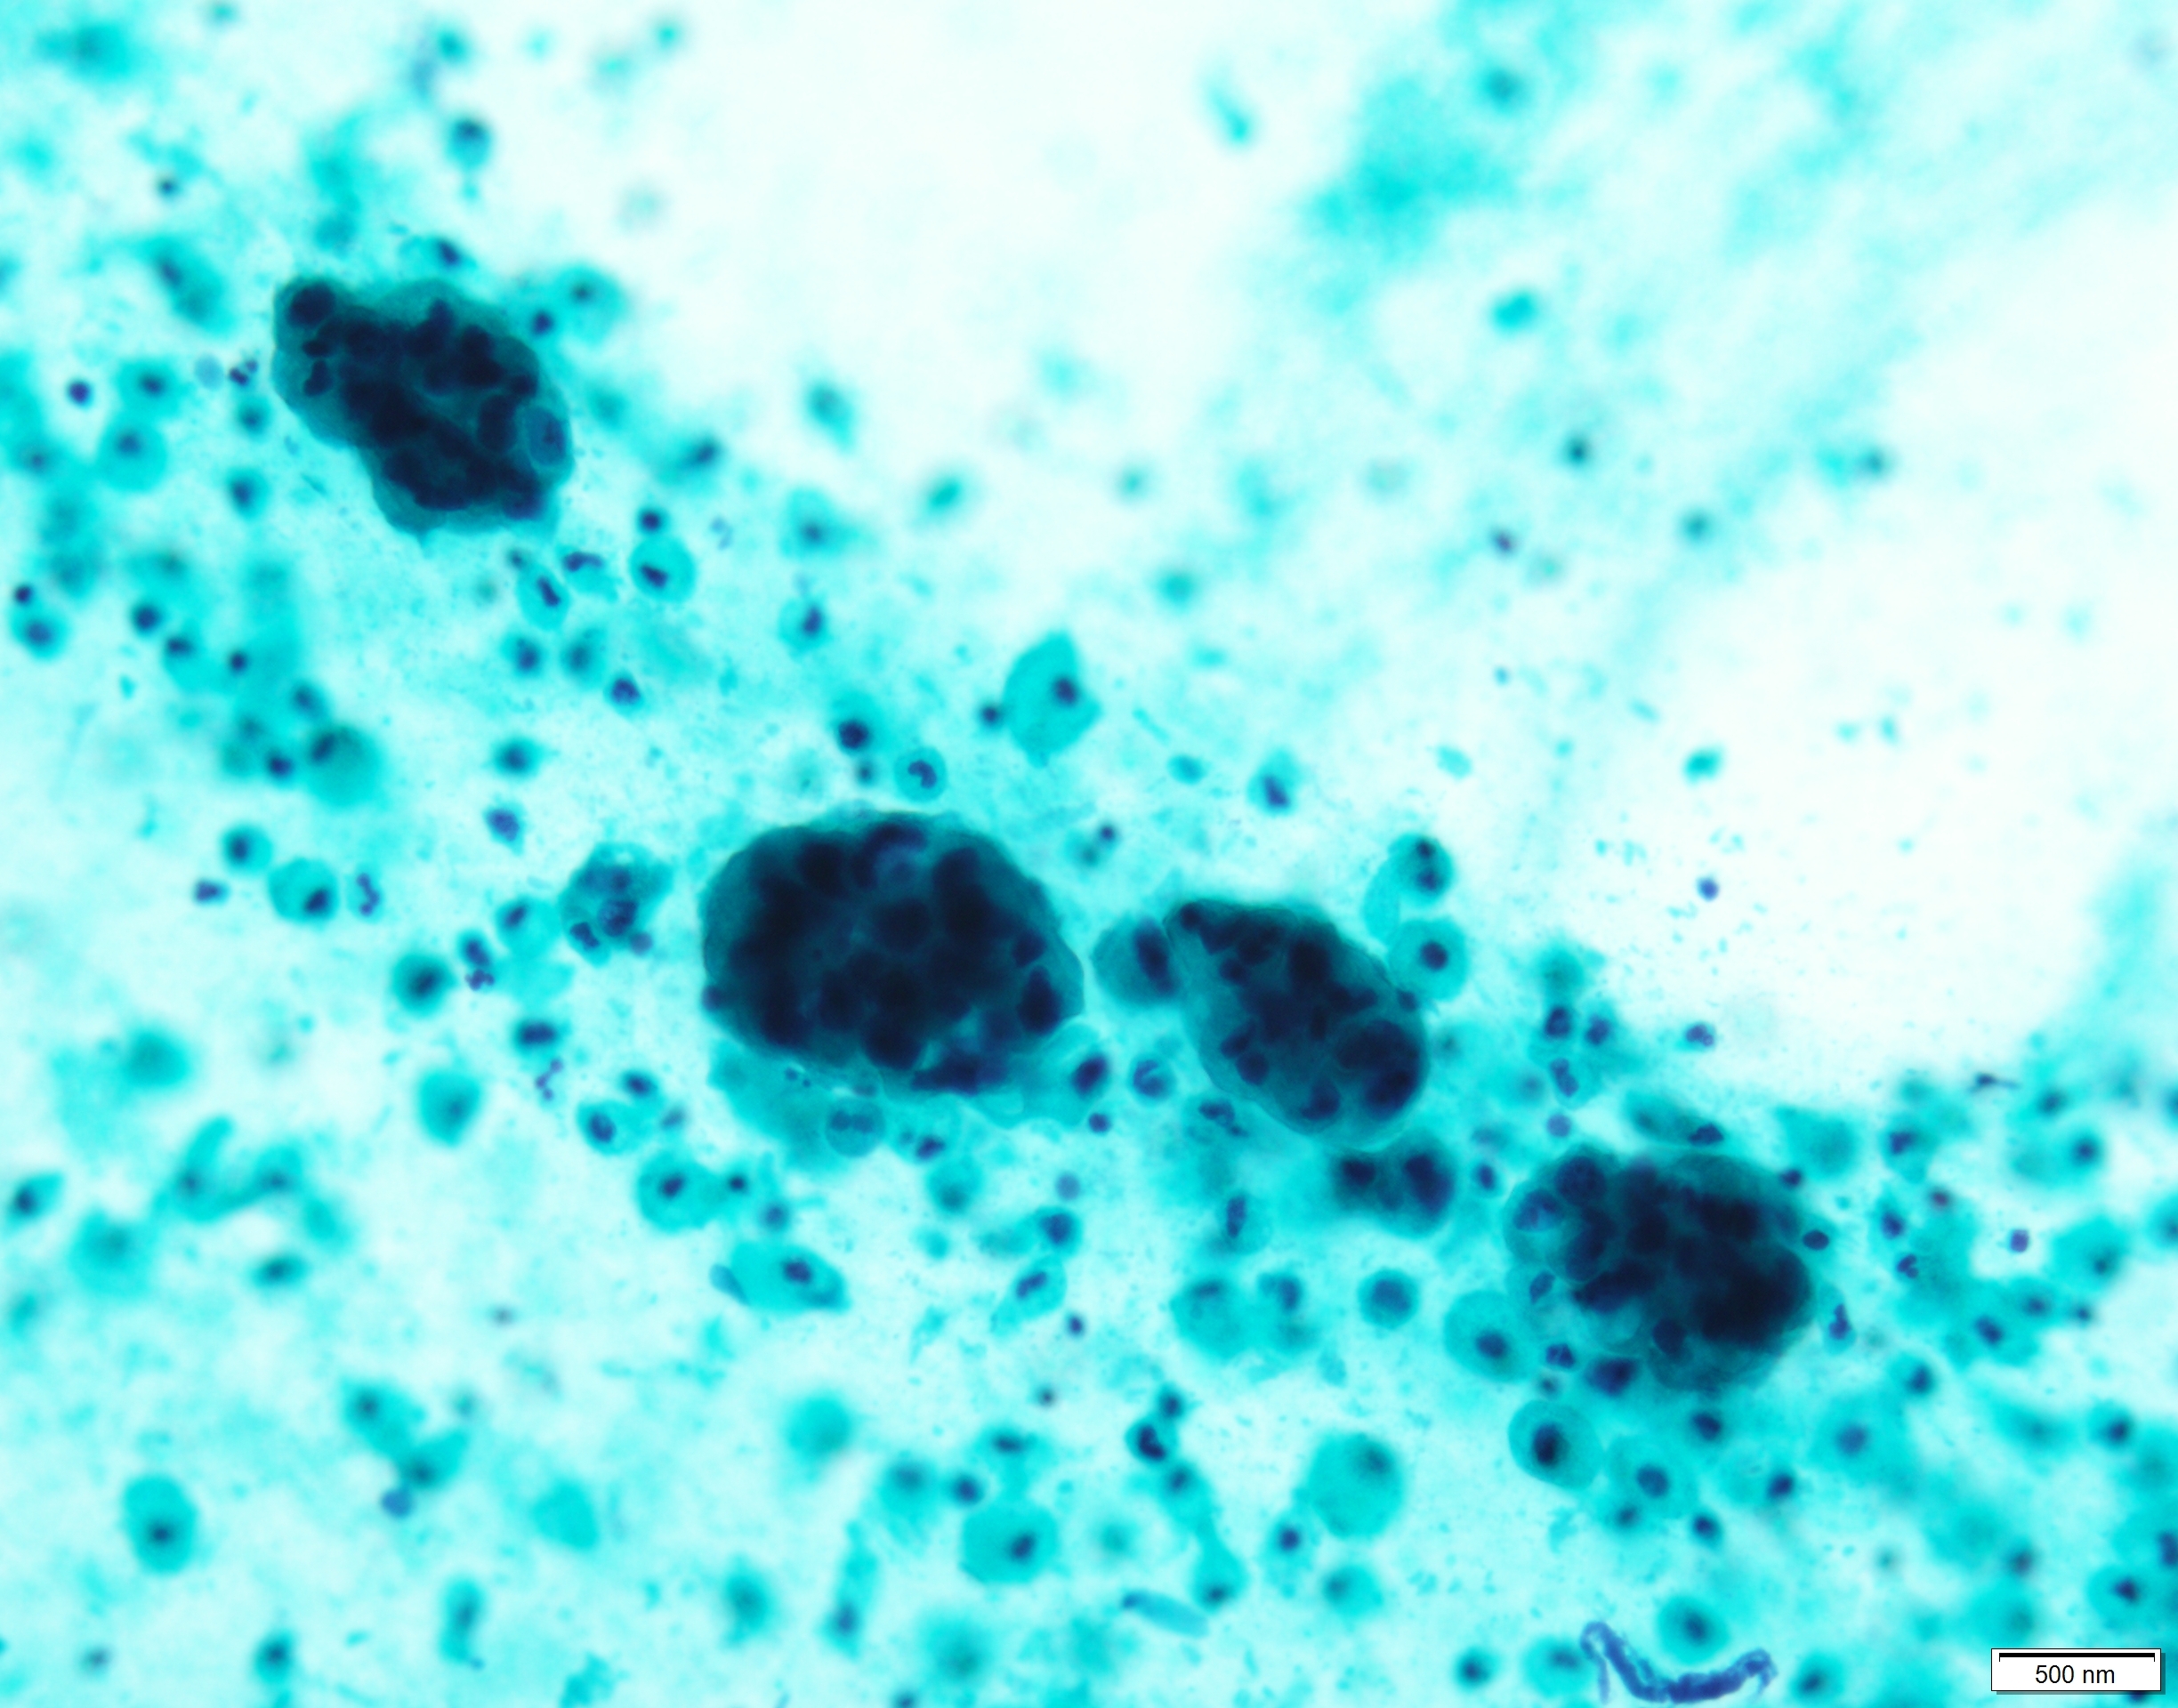

Pap×60